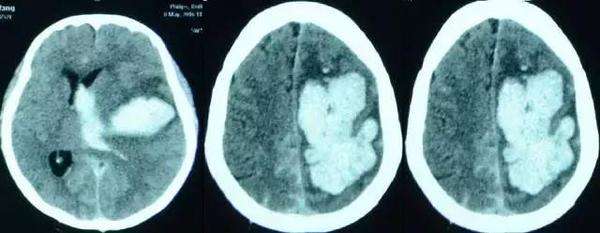

81岁老年脑积水腰大池分流术反致颅内感染颅内出血及走路不能2年余